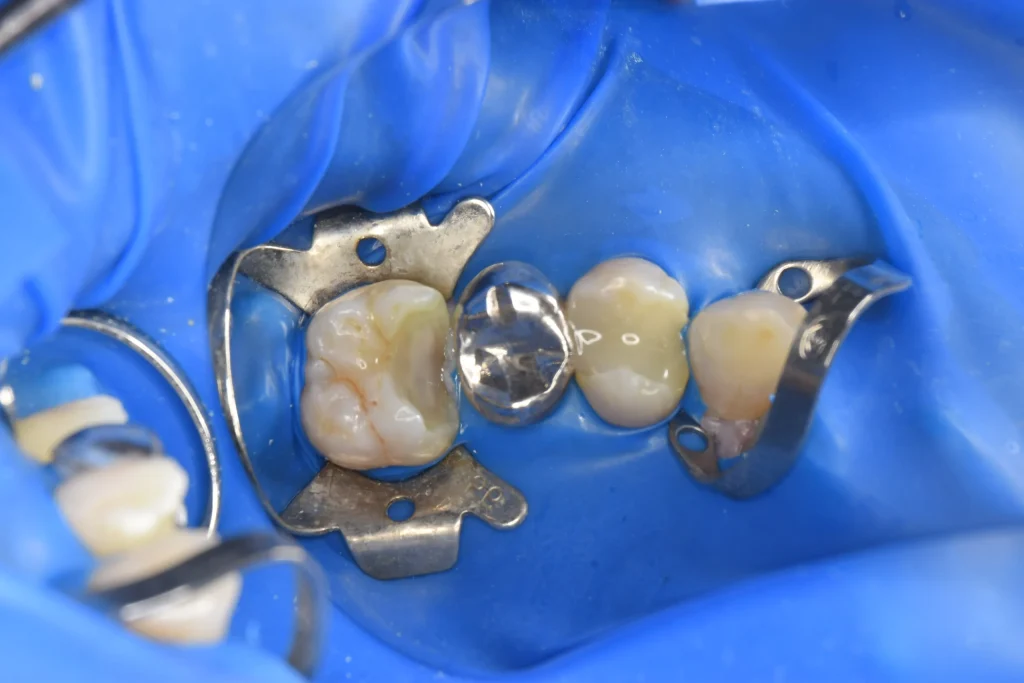

銀歯の前と後ろの歯に大きな穴が空いていることがわかります。患者様は痛みを感じていなかったこともあり、神経を保存する治療を行なっていきます。また、銀歯の下にも虫歯が認められるため、銀歯も一緒に処置をしていきます。

虫歯除去後、神経保護処置を行い、1ヶ月経過をみて痛みがなかったため被せ物治療へ入っていきます。

制作した被せ物の一部です。歯との接触面も精密に仕上がっております。